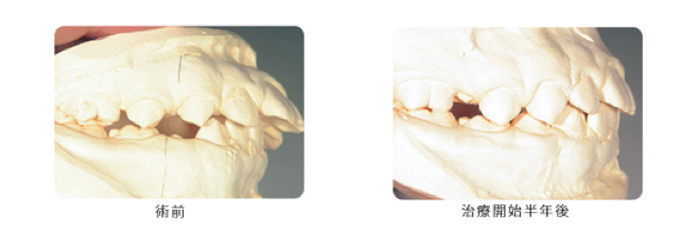

次に実際にこの装置だけ使用して治療した患者さんの例を写真で示します。

この装置は単純な装置ですが、非常に効果があります。成長期を利用して治療を行うことにより、簡単な装置で肉体的、精神的、費用的にも負担が少なく良好な結果が得られます。